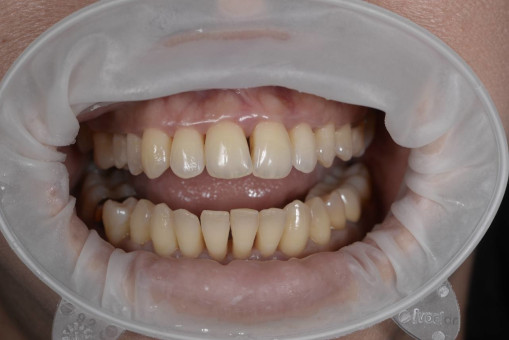

А прежде, чем вы посмотрите фотографии «до» и «после» лечения слизистой оболочки полости рта, проведенных в нашей клинике, хочу поблагодарить большое количество наших пациентов, которые поверили, прониклись нашей концепцией, и мы вместе, именно вместе победили болезни десны, гингивит и пародонтит!

До/после лечения